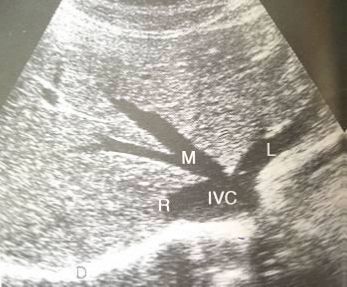

62.下圖為腹部超音波的影像,圖中星號所指為何?

(A)下腔靜脈

(B)門靜脈

(C)腹主動脈

(D)上腔靜脈5c4ec1150bed9.jpg

下腔靜脈(法語:Inferior ven...